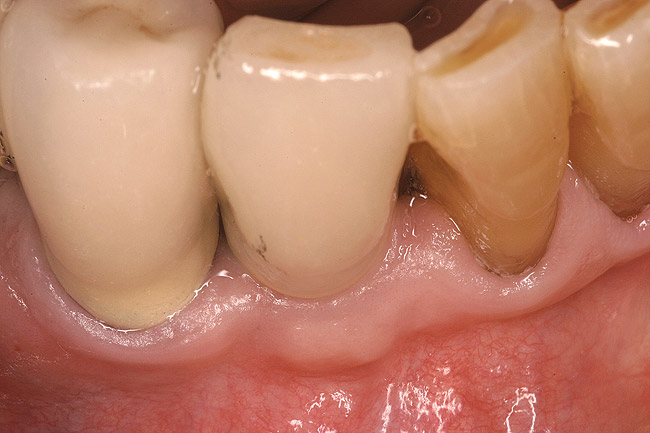

Figure 6  Buccal view of the final restoration on the implant inserted in site No. 27. Note the excellent maintenance of the soft-tissue contours.

Figure 6

Figure 7  Occlusal view 18 months after the final restoration was inserted. Note the amount of preservation of hard and soft tissues.

Figure 7